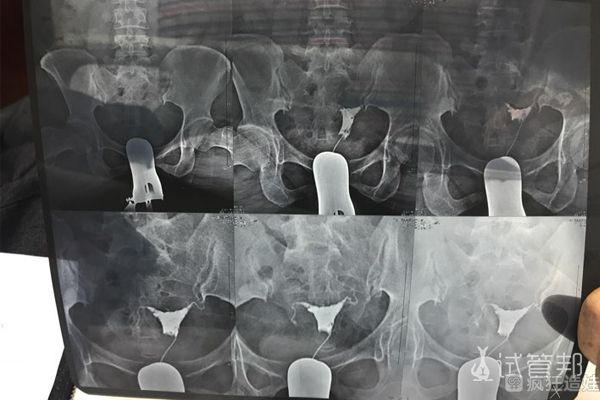

提前还做了宫腔镜检查,内膜没问题,就是有点薄。好在最后涨上去了,顺利进行了移植,第8天看到了灰杠,每天都在加深,第12天血值300多,14天就1000多了,然后一超、二超、NT等检查一路闯关。怀孕整整39周,宝宝终于发动了,顺产诞下宝贝儿子,母子平安,长的特别像我老公,现在的我非常幸福,准备今年再要个二胎。还在试管路上奋斗的姐妹,也要加油鸭~